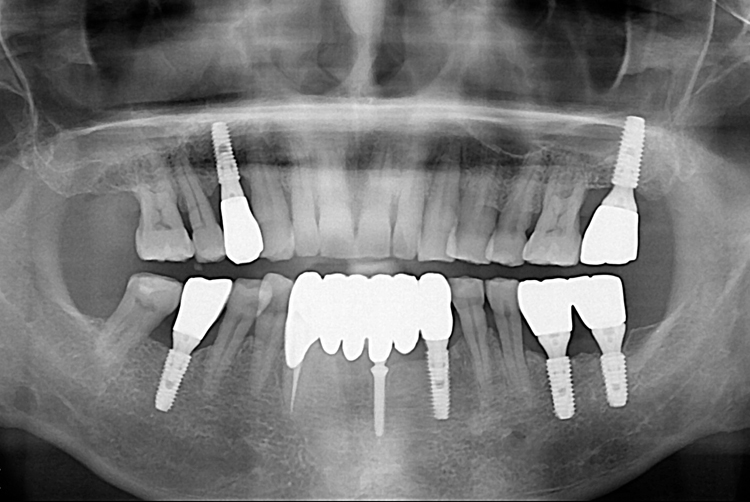

[임플란트] 임플란트

치료전 : 2019-08-21

세종치과는 많은 환자와 다양한 케이스를 바탕으로 항상 편안한 임플란트 수술을 제공하고자 노력하고,

오래동안 튼튼히 쓸 수 있는 임플란트 수술을 가장 큰 목표로 삼고 있습니다